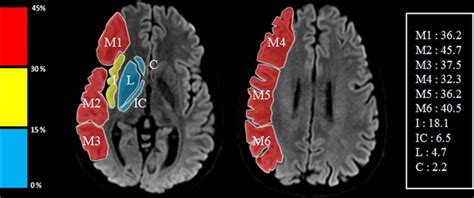

Automated Calculation of the Alberta Stroke Program Early CT Score